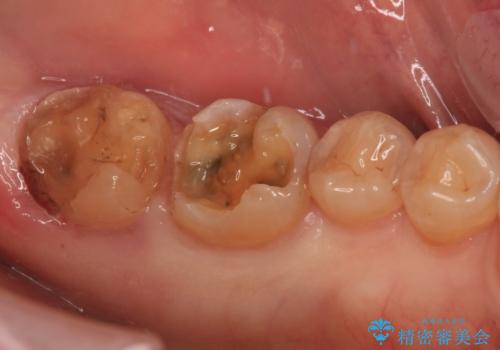

- 奥歯が欠けており、近医でむし歯を指摘されたとのことで来院された患者様です。

1番奥の歯はゴールドインレー周りがむし歯で欠けており、手前の歯はインレーの下にむし歯がある状態でした。